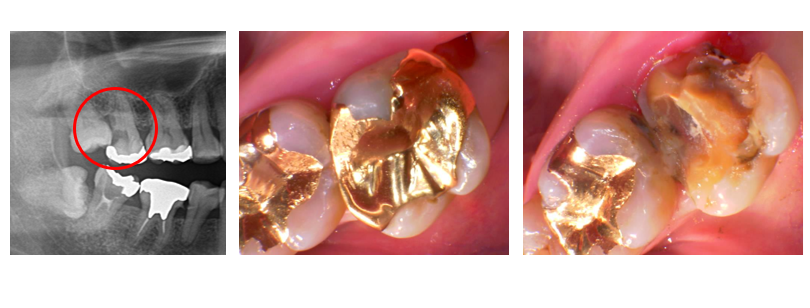

左上のレントゲン写真を見てもらえると。左上の一番左の歯が親知らずになり親知らずが手前の歯に食い込むことで手前の歯が黒く虫歯になっています。痛みの原因は親知らずとその手前の歯の虫歯になります。

真ん中の写真は親知らずを抜いた後の手前の歯の治療前の状態です。見た目はきれいですが金属を除去すると右上の写真のように大きな虫歯によって歯が崩れてしまい原型を留めていません。